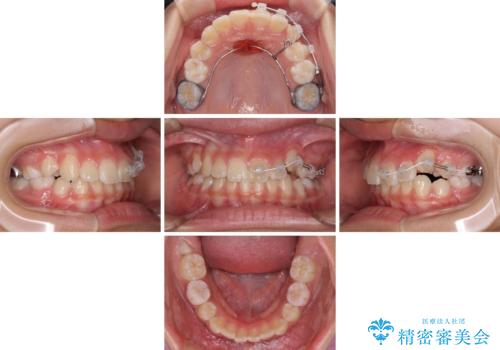

左上の犬歯が低位に埋伏しており、将来八重歯になるリスクが高いと判断されたため、補助装置とワイヤーを用いて犬歯を通常の位置まで移動させることとしました。

今後残っている乳歯が抜け、永久歯が萌出してくるため、調整可能なリンガルアーチを用いて保定を行っています。

12歳臼歯が萌出するまで経過観察を行い、すべての歯が萌出した後に、全顎矯正治療(Ⅱ期治療)を行っていきます。